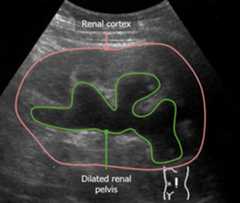

Ultrasound imaging

SometimespatientsPatientsIndividuals participating in the health care system for the purpose of receiving therapeutic, diagnostic, or preventive procedures.Clinician–Patient Relationship with CKD will have a normalGFRGFRThe volume of water filtered out of plasma through glomerular capillary walls into Bowman’s capsules per unit of time. It is considered to be equivalent to inulin clearance.Kidney Function Tests, but ultrasound findings will be consistent with CKD. ThesepatientsPatientsIndividuals participating in the health care system for the purpose of receiving therapeutic, diagnostic, or preventive procedures.Clinician–Patient Relationship are at high risk for developing a ↓GFRGFRThe volume of water filtered out of plasma through glomerular capillary walls into Bowman’s capsules per unit of time. It is considered to be equivalent to inulin clearance.Kidney Function Tests if their disease progresses. Ultrasound findings consistent with CKD include:

• PolycystickidneysKidneysThe kidneys are a pair of bean-shaped organs located retroperitoneally against the posterior wall of the abdomen on either side of the spine. As part of the urinary tract, the kidneys are responsible for blood filtration and excretion of water-soluble waste in the urine.Kidneys: Anatomy

• ChronichydronephrosisHydronephrosisHydronephrosis is dilation of the renal collecting system as a result of the obstruction of urine outflow. Hydronephrosis can be unilateral or bilateral. Nephrolithiasis is the most common cause of hydronephrosis in young adults, while prostatic hyperplasia and neoplasm are seen in older patients.Hydronephrosis

• Small, echogenickidneysKidneysThe kidneys are a pair of bean-shaped organs located retroperitoneally against the posterior wall of the abdomen on either side of the spine. As part of the urinary tract, the kidneys are responsible for blood filtration and excretion of water-soluble waste in the urine.Kidneys: Anatomy with thin cortices

Small kidney with a thin cortex

Image: “Ultrasonography of chronic renal disease caused by glomerulonephritis” by Kristoffer Lindskov Hansen, Michael Bachmann Nielsen and Caroline Ewertsen. License:CC BY 4.0, edited by Lecturio.